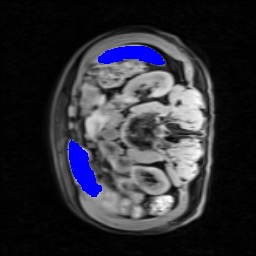

Transformers have made remarkable progress towards modeling long-range dependencies within the medical image analysis domain. However, current transformer-based models suffer from several disadvantages: (1) existing methods fail to capture the important features of the images due to the naive tokenization scheme; (2) the models suffer from information loss because they only consider single-scale feature representations; and (3) the segmentation label maps generated by the models are not accurate enough without considering rich semantic contexts and anatomical textures. In this work, we present CASTformer, a novel type of generative adversarial transformers, for 2D medical image segmentation. First, we take advantage of the pyramid structure to construct multi-scale representations and handle multi-scale variations. We then design a novel class-aware transformer module to better learn the discriminative regions of objects with semantic structures. Lastly, we utilize an adversarial training strategy that boosts segmentation accuracy and correspondingly allows a transformer-based discriminator to capture high-level semantically correlated contents and low-level anatomical features. Our experiments demonstrate that CASTformer dramatically outperforms previous state-of-the-art transformer-based approaches on three benchmarks, obtaining 2.54%-5.88% absolute improvements in Dice over previous models. Further qualitative experiments provide a more detailed picture of the model's inner workings, shed light on the challenges in improved transparency, and demonstrate that transfer learning can greatly improve performance and reduce the size of medical image datasets in training, making CASTformer a strong starting point for downstream medical image analysis tasks.